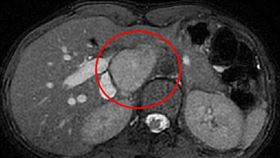

女心悸、盜汗 罹罕病「副神經節瘤」

一名25歲年輕女性因膀胱炎反覆感染就醫,結果意外發現...